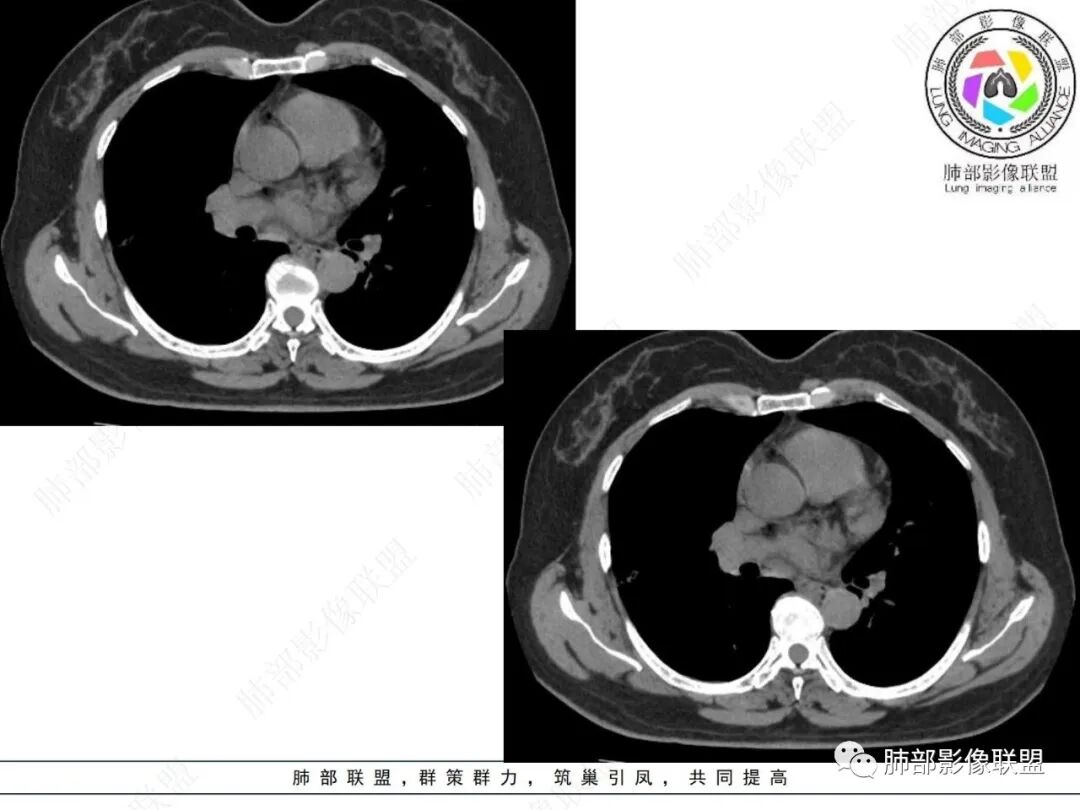

2.影像特点:

右肺上叶胸膜下混合磨玻璃团片影。

周围磨玻璃部分间杂条索状高密度区,密度欠均匀(可疑重力分布趋势),其磨玻璃影边界大多较清楚或可分辨,部分“L型”边缘,提示小叶间隔阻挡可能。血管穿行自如,可疑远端支气管进入。

实性部分较密实,不规则,隐约见棘突或刺状突起,未见钙化、空洞或液化区,实性边缘可见斑状略低密度间隙(借用王兆宇老师课件,称其呈“松软”的形态)。动脉期实性部分较明显不均匀强化,如果有完整增强图,还可以观察内部血管情况。

纵隔窗相对肺窗病灶相对小,仅部分实性影呈现。病灶张力不高,相邻胸膜增厚(糊墙),未见明显胸膜牵拉凹陷。

未见卫星病灶,远处未见磨玻璃结节影。

双肺门及纵隔未见明显增大淋巴结。心包及胸腔未见积液。